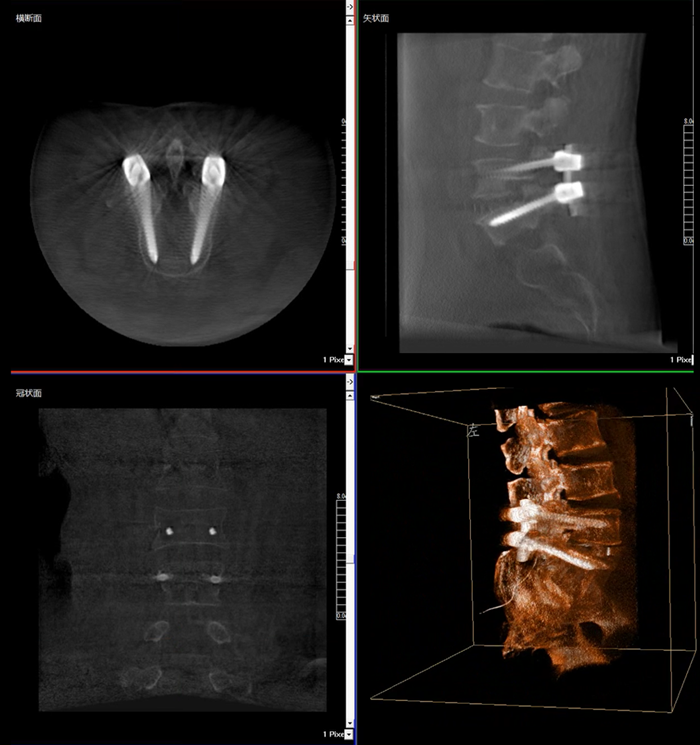

移動式三維C形臂,又稱骨科三維C臂,就是將傳統二維與“類CT模式”相結合的升級版C形臂,能在術中快速地生成橫斷面、矢狀面、冠狀面斷層圖像和三維立體圖像。通過不同方位的斷層圖像,能夠更清晰、完整地顯示椎體及其附件的解剖學結果,直觀地分析病變與周圍組織的立體空間關系,三維斷層成像能夠使手術模擬和手術方案的制定更加準確。

術中三維影像

而三維影像的MPR圖像組可以通過不同平面的切分,使成像區內更豐富的信息得以呈現。尤其是二維影像無法涉及的橫斷面,提供了另一個空間維度的信息量。

在MPR圖像中,冠狀面、矢狀面和橫斷面的信息大大提高了醫生對于病灶區以及手術效果的判定。